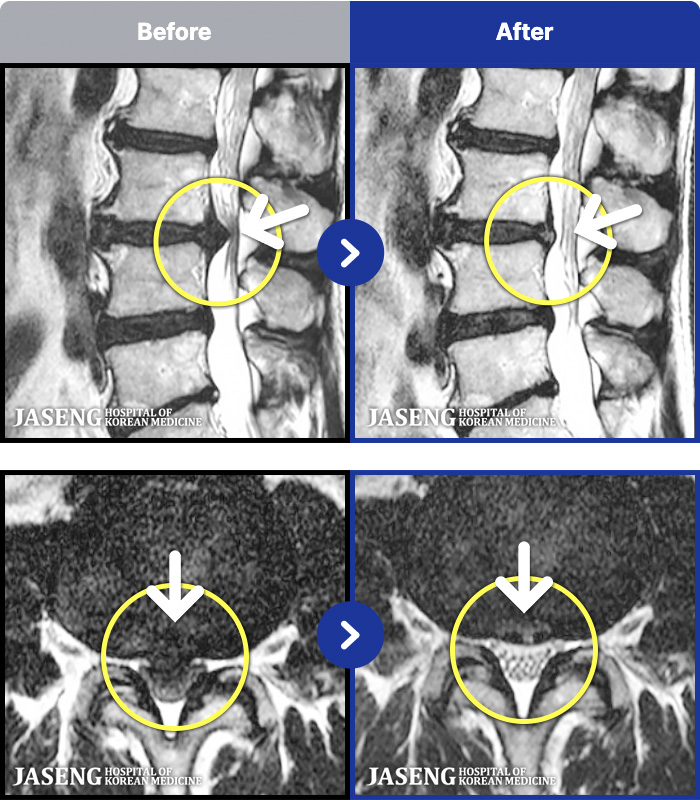

MRI ġ

MRI ũ ʸ Ȯϼ.